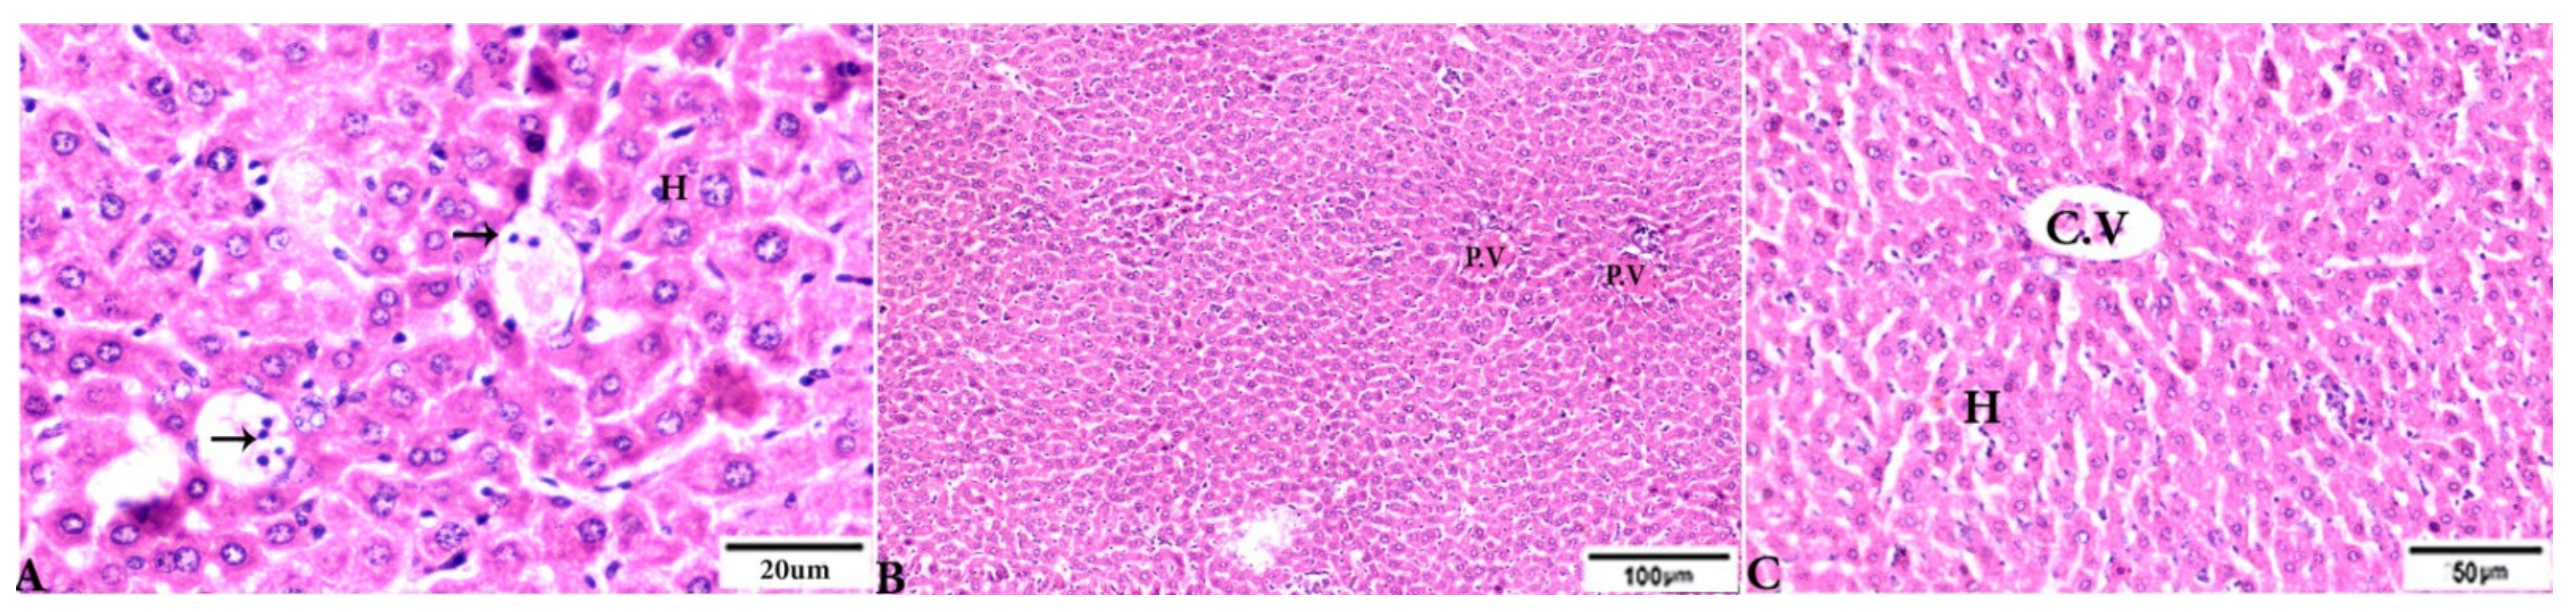

To investigate the effects of propolis, WGO, or the combination of both substances on T. gondii-induced infection, liver (Figure 3, Figure 4, Figure 5 and Figure 6) and lung (Figure 7, Figure 8 and Figure 9) tissues from different groups were examined histopathologically. Liver sections (Figure 3A,B) from control noninfected mice (G1) demonstrated normal hepatic architecture, comprising a normal central vein and normal sinusoids between hepatic cellular cords. Normal portal triad structures (hepatic artery, portal vein, and bile duct) were also observed. In contrast, severe damage, multiple tissue cysts, congested vessels, obvious inflammation, coagulative necrotic foci, and numerous tissue cysts were observed in the liver (Figure 3C–F) of T. gondii-infected untreated mice (G2). Attenuated or moderate histological evidence (moderate inflammation and fewer necrosis foci) in hepatic tissues and a relatively high number of tachyzoites (Figure 4A–D) were observed in liver tissues of T. gondii-infected mice treated with propolis (G3). Treatment with WGO only (G4) ameliorated the histopathological changes (mild inflammation and normal hepatocellular structure), and a lower number of tachyzoites was observed (Figure 5A). Notably, liver tissue sections from T. gondii-infected mice treated with a combination of propolis and WGO appeared morphologically indistinguishable from uninfected controls (Figure 5B,C). Quantitative and semiquantitative analysis of the severity of inflammation, necrosis of liver sections, and the number of parasites present in tissue fields of different groups was performed (Figure 6). The results showed a significant increase in pathological lesions in T. gondii-infected untreated mice (G2) compared with the control group, whereas significantly reduced pathologic alterations were observed in the propolis (G3), WGO (G4), and combination treatment (G5) groups.

Figure 3.

Photomicrograph of H&E-stained liver tissue sections from mice in the experimental groups: (A,B): Liver sections from the negative control group (G1) demonstrating: (A): normal hepatic architecture comprising a normal central vein (C.V), sinusoids (S), and hepatocytes (H); and (B): normal portal triad structures: hepatic artery (arrowhead), portal vein (P.V), and bile duct (zigzag arrow). (C–F): Liver tissue sections from mice in the Toxoplasma gondii-infected positive control group (G2) showing: (C): severe vascular congestion (stars), focal mononuclear cellular aggregations (selected squares), and coagulative necrosis in hepatocytes; (D): dilated and congested PV, longitudinal fibrous tracts connected between P.V (arrows); (E,F): congested C.V, multiple bradyzoites (zigzag arrows), tissue cyst (arrowhead), and marked Kupffer cell reactions (E, arrowheads). The scale bar is provided below each image.

Figure 5.

Photomicrograph of H&E-stained liver tissue sections from mice in the experimental groups: (A): liver tissue sections from mice in the Toxoplasma gondii-infected group treated with wheat germ oil (G4) showing normal hepatocellular structure (H); parasitic tissue cyst contains bradyzoites (arrows). (B,C): Liver tissue sections from mice in the combined propolis and wheat germ oil treatment group (G5) showing: (B): normal portal structure with normal portal vein (P.V), normal central vein (C.V), and normal hepatocytes (H). The scale bar is provided below each image.